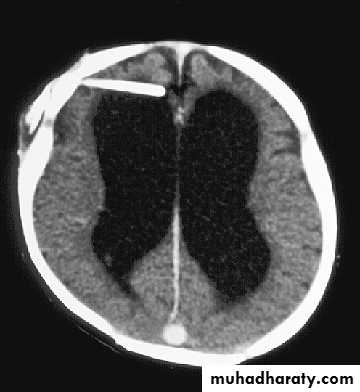

Hydrocephalus

37

Normal ventricles and hydrocephalus

Hydrocephalous

• accumulation of cerebrospinal fluid (CSF) in the ventricles, or cavities, of the brain .

• Non communicating :• Fluid cant pass to the subarachnoid space

• In this type is blockage of the aqueduct of sylvius .